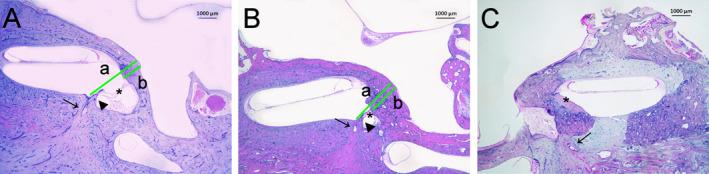

We selected archival temporal bones from donors with otosclerosis. We evaluated the degree of RW obliteration using a semi-quantitative scale and the location of the foci within the temporal bone, and whether the foci were continuous or isolated.

Most of the foci were located anteriorly to the oval window (89.2%), while RW area involvement was seen in 26.9% of the ears. In cases with fenestral foci, 68.1% directly involved and/or fixed the footplate. Among donors with bilateral otosclerosis, foci affected both ears in a similar pattern in 64.2%. Among donors with RW involvement, ones with continuous, large lesions that extended from the oval window associated with complete RW obliteration, while ones with smaller degrees of obliteration had solitary foci scattered within the otic capsule.

Our results demonstrate a high rate of RW involvement in cases of otosclerosis. Ears with continuous lesions extending from the oval window region to the RW area were more likely to present with complete RW obliteration. These results provide insights that could lead to better prognostic assessment of patients with otosclerosis in the future.